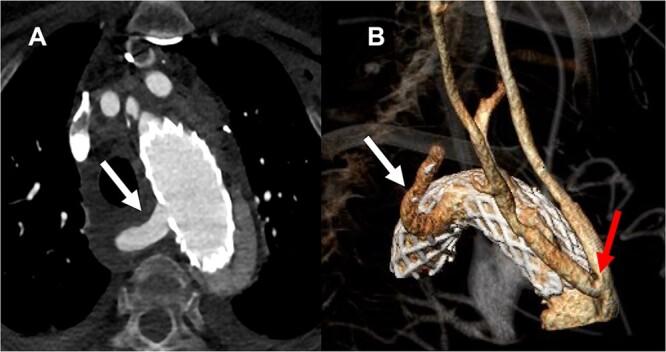

Aberrant right subclavian artery is a rare congenital aortic arch anomaly. We report on a case of type A aortic dissection and aberrant right subclavian artery. The 65-year-old female patient received a replacement of the ascending aorta and arch repair using an uncovered AMDS (Ascyrus Medical Dissection Stent; CryoLife Inc., Kennesaw, GA, USA) with debranching of both common carotid arteries. Postoperative computed tomography scan revealed regular aortic blood flow with the unrestricted carotid artery and aberrant right subclavian artery perfusion.

异常右锁骨下动脉是一种罕见的先天性主动脉弓畸形。我们报告一例 A 型主动脉夹层和异常右锁骨下动脉。该 65 岁女性患者接受了升主动脉置换和使用未覆膜的 AMDS(Ascyrus Medical Dissection Stent;CryoLife Inc.,佐治亚州肯尼索)进行的弓部修复,同时对双侧颈总动脉进行了分支重建。术后计算机断层扫描显示主动脉血流正常,颈动脉和异常右锁骨下动脉灌注不受限制。